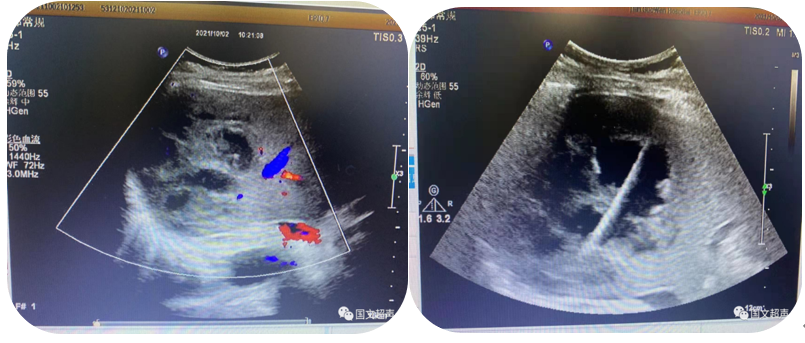

1.超聲引導下穿刺活檢

超聲的實時引導下,穿刺針插入腫大淋巴結、疑似占位等特定部位進行組織抽吸、切割獲取病理標本幫助疾病診斷。

超聲引導下淺表淋巴結穿刺活檢